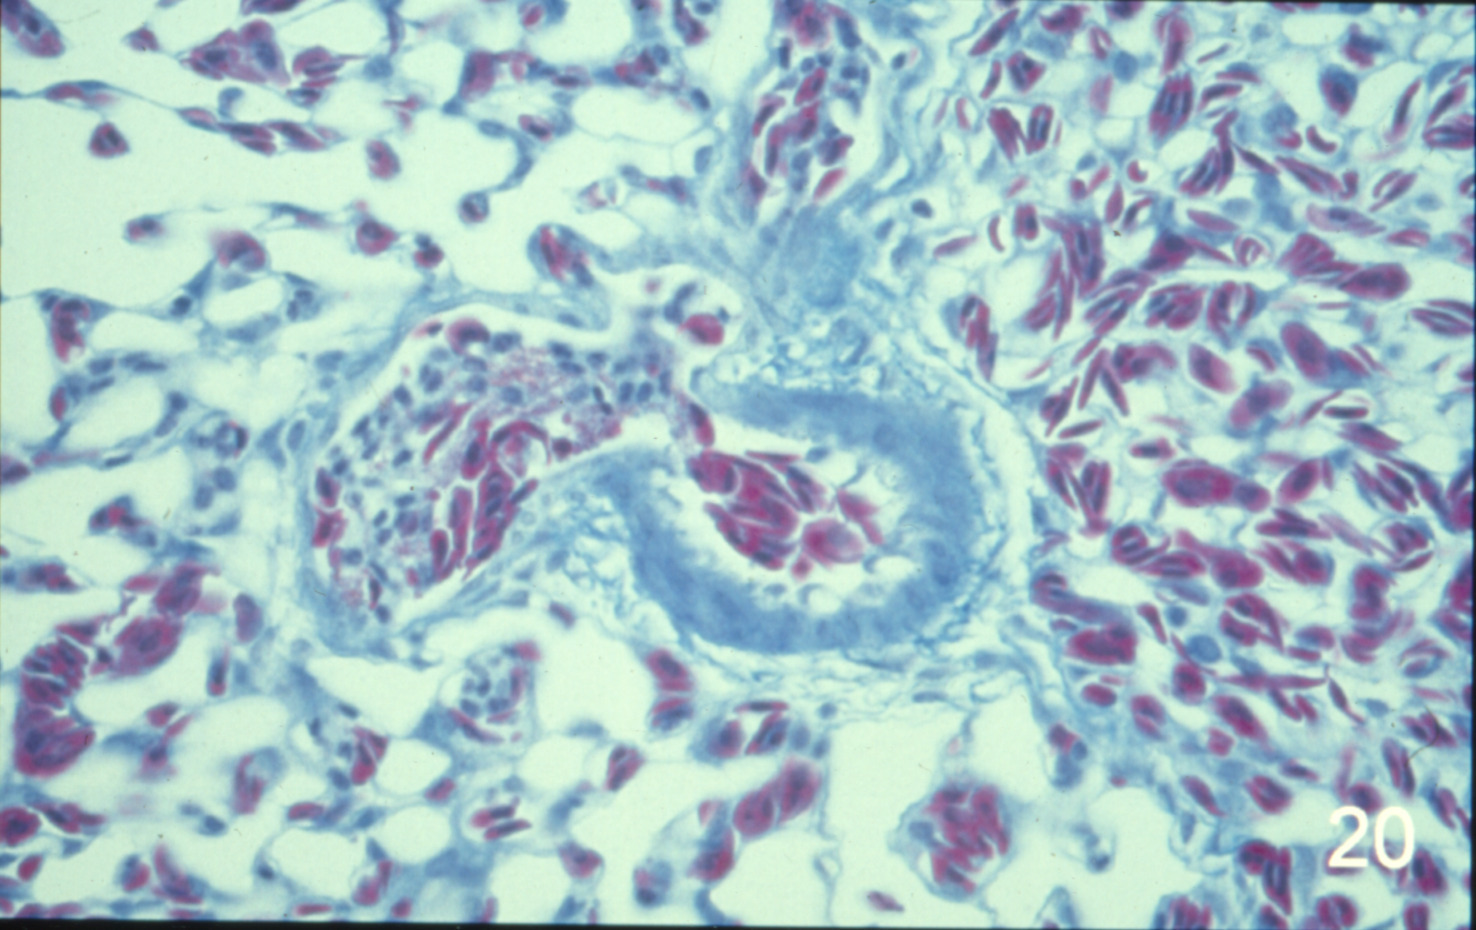

Ascites syndrome in meat-type chickens (slide study set no. 23)

Chickens--Diseases Ascites

Slide Study Set #23, Ascites Syndrome in Meat-Type Chickens (includes 27 color slides), 2001